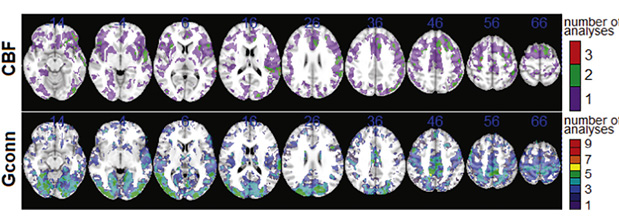

Afin de mieux interpréter le schéma spatial des effets de commotion cérébrale observé pour CBF (Fig. 1) et Gconn (Fig. 2), la Fig. 3 ci-dessous illustre des cartes par voxels comptant le nombre d'analyses de biomarqueurs cérébraux ayant détecté des effets de commotion importants.

Les régions du cerveau où le couplage avec des biomarqueurs sanguins est associé de la manière la plus fiable aux effets de commotion cérébrale. Les cartes en couleurs illustrent le nombre d'analyses dans lesquelles les voxels montrent un effet de commotion cérébrale important pour le flux sanguin cérébral (CBF) sur la base des résultats de la Fig. 1 et pour la connectivité fonctionnelle globale (Gconn) sur la base des résultats de la Fig. 2.

Les différentes modalités d'imagerie fonctionnelle utilisées dans cette étude, y compris l'ASL et l'IRMf à l'état de repos, fournissent des informations complémentaires sur les réponses neurophysiologiques possibles liées aux biomarqueurs sanguins après SRC. Sur la base des distributions spatiales rapportées (Fig. 3), les résultats indiquent que la SRC est principalement associée à la covariance de biomarqueurs sanguins et de CBF fronto-temporaux. Les résultats concordent avec le fait que ces régions de matière grise sont vulnérables aux blessures primaires causées par des impacts à la tête, des études antérieures de neuro-imagerie montrant des effets fronto-temporaux associés à la fois à une blessure aiguë et à des antécédents de commotion. Inversement, les analyses de Gconn ont montré le plus grand couplage cerveau-biomarqueur dans les régions occipito-pariétales.

Par conséquent, les effets des lésions neurologiques sur la connectivité fonctionnelle concernent principalement les zones associées à la fonction visuelle et à l’orientation visuo-spatiale. Ces résultats sont également cohérents avec des études antérieures qui ont rapporté des effets de commotion cérébrale sur la connectivité fonctionnelle au repos dans les régions occipitales et pariétales.

Les différentes modalités d'imagerie fonctionnelle utilisées dans cette étude, y compris l'ASL et l'IRMf à l'état de repos, fournissent des informations complémentaires sur les réponses neurophysiologiques possibles liées aux biomarqueurs sanguins après SRC. Sur la base des distributions spatiales rapportées (Fig. 3), les résultats indiquent que la SRC est principalement associée à la covariance de biomarqueurs sanguins et de CBF fronto-temporaux. Les résultats concordent avec le fait que ces régions de matière grise sont vulnérables aux blessures primaires causées par des impacts à la tête, des études antérieures de neuro-imagerie montrant des effets fronto-temporaux associés à la fois à une blessure aiguë et à des antécédents de commotion. Inversement, les analyses de Gconn ont montré le plus grand couplage cerveau-biomarqueur dans les régions occipito-pariétales.

Par conséquent, les effets des lésions neurologiques sur la connectivité fonctionnelle concernent principalement les zones associées à la fonction visuelle et à l’orientation visuo-spatiale. Ces résultats sont également cohérents avec des études antérieures qui ont rapporté des effets de commotion cérébrale sur la connectivité fonctionnelle au repos dans les régions occipitales et pariétales.